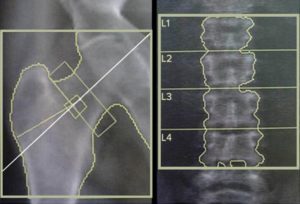

New knowledge on viral infections and bone fractures

A quarter of patients who are infected with human immunodeficiency virus (HIV) in the United States are also infected with Hepatitis C virus…